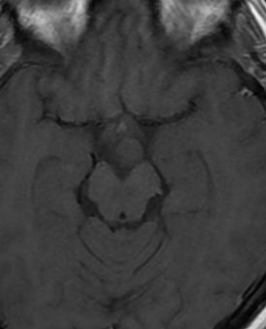

Tuber cinereum hamartoma

IRM

- Masse du tuber cinereum (entre corps mamillaires et tige pituitaire)

- IsoT1, Iso T2

- Pas de prise de contraste Gd+